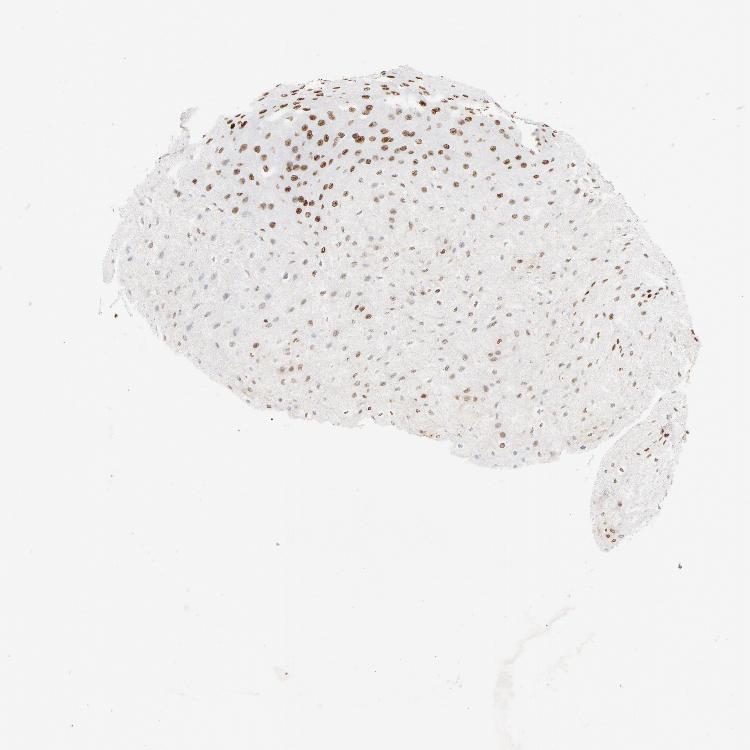

ESOPHAGUS - Antibody stainingi

Antibody staining in the annotated cell types in the current human tissue is reported as not detected, low, medium, or high, based on conventional immunohistochemistry profiling in selected tissues. This score is based on the combination of the staining intensity and fraction of stained cells.

Each image is clickable and will lead to virtual microscopy that enables deeper exploration of all samples and also displays staining intensity scores, fraction scores and subcellular localization as well as patient and tissue information for each sample.

Antibody HPA003506Antibody HPA053314Antibody CAB037206

Squamous epithelial cells HighMediumHigh